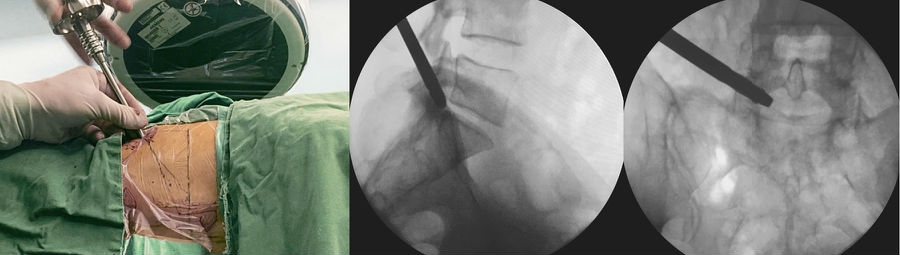

4. 穿刺

以L5~S1为例,根据髂嵴的高低,针尾向头侧倾斜约 40°~60°,外展角约 30°~50°,定位针在正位X线透视下刚好位于后背正中的棘突连线上,侧位X线透视下则紧贴上关节突腹侧,下缘位于下位椎体的后上缘。(图6)

5. 穿刺点

做大约1cm皮肤切口,用导丝置换穿刺针,沿导丝用扩张器逐级扩大软组织。(图7、图8)

6. 置入定位器

在上关节突上打孔,退出扩张器,再磨除部分关节突关节,逐级扩大椎间孔。(图9~图13)

图3 定位板前后位X线片标定靶点和穿刺方向

A. 术前定位板标记体表位置;B.定位板X线射片投影图

图5-图9 A:使用利多卡因进行局部分层麻醉(皮肤、皮下组织、筋膜、关节突周围);B:穿刺针X线片侧位投影图;C:穿刺到位后交换导丝;D:导丝引导下通过导杆、三级套管扩张肌肉及软组织;E:导丝引导下交换Tom针,定位上关节突

图10 Tom针定位上关节突

A. Tom 针定位上关节突;B.Tom 针X 线片侧位投影图;C.Tom 针X线片前后位投影图

图11-图13 6mm扩孔骨钻扩孔过程中;6mm扩孔骨钻侧位X线片投影图;8mm扩孔骨钻前后位X线片投影图